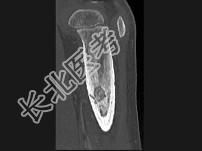

- 单项选择题男,30岁, 左大腿疼痛1年余,夜间或休息加重, 口服止痛药可缓解,结合图像, 最可能的诊断是 ( )

B、骨样骨瘤